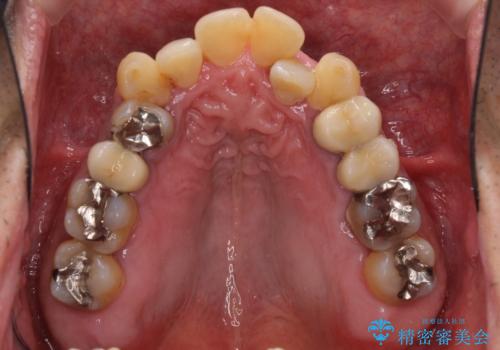

全体的に中等度の歯周病と診断されたため、歯周外科処置やインプラントによる咬合回復から進めて行き、矯正治療による歯列改善を行った後にオールセラミッククラウンにて補綴することとしました。

歯槽骨の再生治療を行ったため、外科処置後の静置期間がながくなり、4年弱の治療期間となりました。